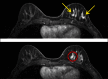

Figure 3.

Two gadolinium-enhanced MR images of the left breast demonstrate multiple areas of nonmasslike enhancement (yellow arrows) within the lower inner and lower outer quadrants of the left breast. An area of masslike enhancement (red circle) is also identified at the 7:00 position.